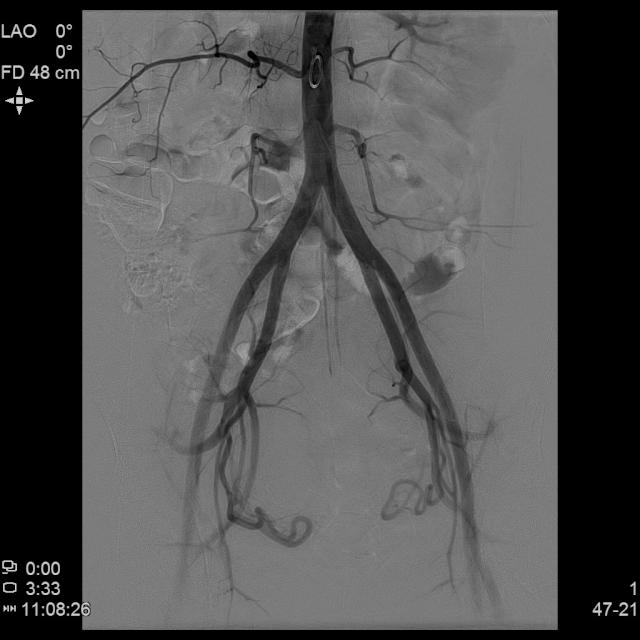

前列腺介入栓塞手术是目前比较新的一种治疗前列腺增生的手术方法。此手术通过患者股动脉穿刺,穿刺成功后置入特殊的导丝、导管,通过造影剂(X线下显影)找到供应前列腺的血管。将供应前列腺的血管通过特殊的弹簧圈或者海绵栓塞。阻断前列腺血管供应,使前列腺缺血、萎缩,改善患者排尿困难等情况。此手术是对高龄、高危的前列腺增生治疗的又一选择。

前列腺动脉栓塞术操作的关键是找到前列腺的供血动脉,以免误栓前列腺周围的正常血管,前列腺由多支动脉参与供血,给动脉栓塞带来了不便。前列腺动脉栓塞术适用于:年龄>50岁,明确为前列腺增生所致的中重度症状、经药物治疗6个月以上效果不佳、前列腺体积>40g、有外科或微创外科治疗指征者。